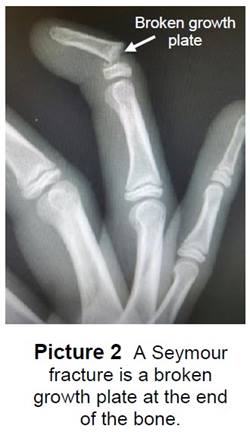

- Seymour Fracture - a break in the growth plate (Picture 2).

- Tuft fracture - a break in the bone closest to the tip of the finger.

- Both types of fingertip fractures are treated with a splint or cast.